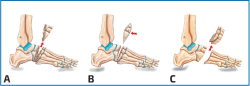

Técnica de Japas

La osteotomía/artrodesis de Japas, descrita en 1968(8), es una intervención que genera una osteotomía en V del mediopié que se extiende desde la cuña medial al cuboides. Se debe evitar englobar la articulación talonavicular, así como la tarsometatarsal, aunque en pacientes que presenten una flexión plantar marcada del primer radio esta se puede extender hasta la base del primer metatarsiano (Figura 3).

Técnica de Akron/Myerson

Es una osteotomía en cuña de base dorsomedial que pasa a través de las cuñas y el cuboides. No se extrae hueso del cuboides y de esta forma se genera una corrección angular por la cuña dorsomedial, pudiendo asociarse rotación a este nivel tarsiano.

Artrodesis de la tarsometatarsiana (Lisfranc)

De utilidad en el pie cavo anterior con talón neutro. Típicamente, presenta el primer radio plantar flexionado con el ápice en Lisfranc.

Técnica de Jahss

La descripción original la propuso M. Jahss(9); consiste en 3 incisiones separadas longitudinales del mediopié sobre la primera, tercera y quinta articulaciones tarsometatarsianas. Existe una alternativa con 2 incisiones de mayor longitud ubicadas sobre la faceta medial de la primera cuneometatarsiana y sobre la articulación cuboides-quinto metatarsiano. Se debe prestar atención a los paquetes neurovasculares tanto plantares como dorsales. Se realiza una osteotomía en cuña de base dorsal alineada con las articulaciones tarsometatarsales (Figura 4).

Figura 2. Diversos tipos de osteotomía descritos para el tratamiento del pie cavo anterior. A: técnica de Japas; B: Akron/Myerson; C: técnica de Jahss.